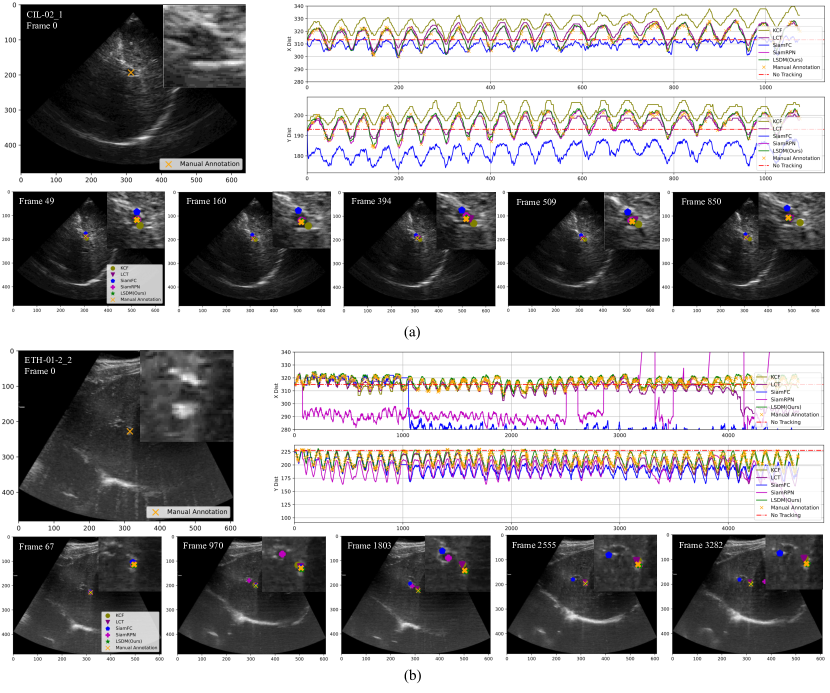

Figure 6: Qualitative comparison of different baseline models and the proposed LSDM by tracking validation on the CLUST2D training set. We select a representative dataset entry to demonstrate LSDM superior tracking performance. We show the start frame at frame 0 (top-left), landmark center coordinate tracklet comparison (top-right) and selected frames with landmark tracking results (bottom). We can observe a stable and accurate tracking performance of LSDM, while other baselines fail at accumulating tracking error through the whole sequence. Supplementary V summarizes other tracking results and their visualization. Best viewed in color.

LSDM achieves accurate tracking by learning an optimized deformation between the exemplar and follow-up instances, which can help the downstream tracking network for finding the best candidate with plausible deformation. As shown in Table I, LSDM outperforms several baselines. Traditional correlation filtering based methods such as KCF and LCT cannot achieve satisfactory tracking performance on large-scale datasets due to various challenges. Even though methods like LCT incorporate historical information for updating tracking kernels, these baselines cannot produce accurate tracklets, lacking high-dimensional representation. Compared with tracking methods based on siamese networks such as SiamFC and SiamRPN, LSDM outperforms with lower tracking error in both mean and standard deviation. Specifically, LSDM outperforms SiamRPN with 1.61 lower in mean and 0.88 lower in standard deviation. Recall that SiamRPN contains an extra branch for minimizing the regression loss of the tracking object location directly. This indicates that only measuring the size (such as bounding box regression in SiamRPN) of the tracking object is not enough for accurate position estimation while an optimized deformation can be used as a prior for searching objects to improve tracking accuracy. We report an example of tracklet comparison in Fig. 6 and additional examples in Fig. S3 Supplementary E. We can observe that our proposed LSDM can track the landmark accurately within long time ultrasound sequences while the other baselines fail in all different situations, e.g. distracted by other landmarks with a high visual similarity in Fig. 6, cannot handle the landmark deformation effectively resulted in accumulative tracking errors in Fig. S3 Supplementary E.